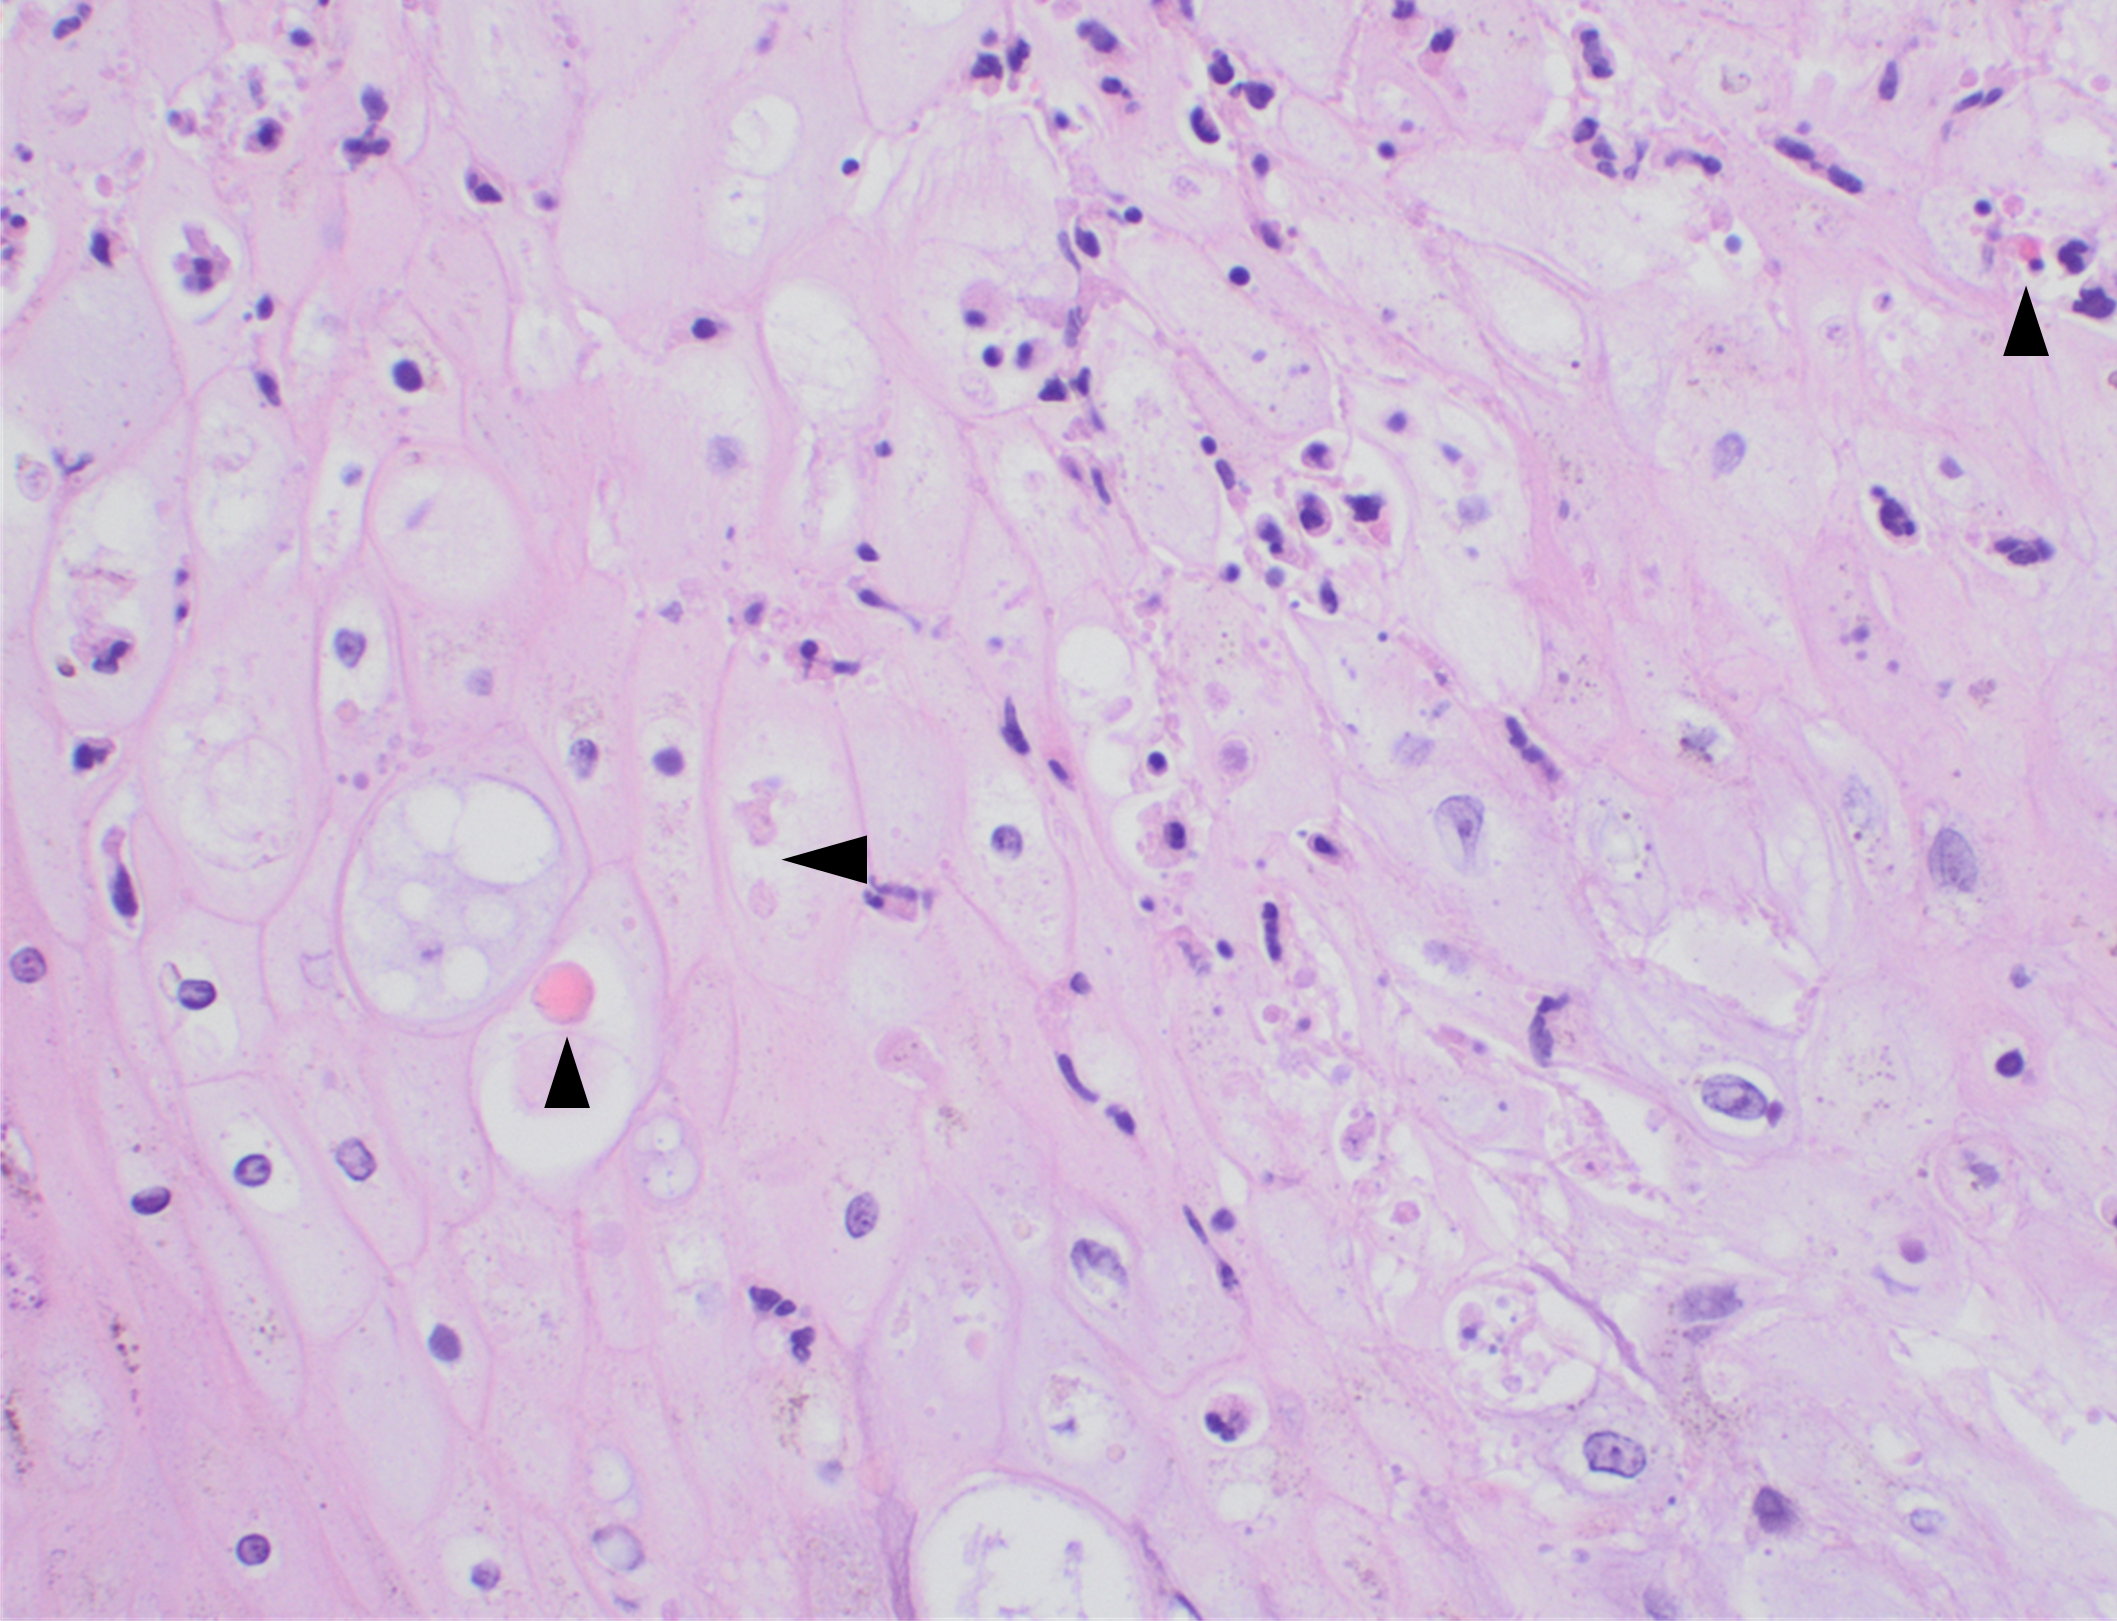

Figure 3. Histopathologic findings of MPOX in a biopsy of a skin lesion (40x magnification, H&E).

High power magnification of viral inclusions, guarnieri bodies, (arrowheads) in a background of necrotic keratinocytes and neutrophilic infiltrate.